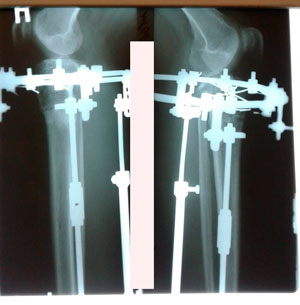

Рентген перед фиксацией

Вложения

рентген 60 дней

Рентген и ножки перед снятием аппаратов

Дата операции - 15.07.2019г.

Дата снятия аппаратов - 15.10.2019г.

Срок сращения 90 дней.